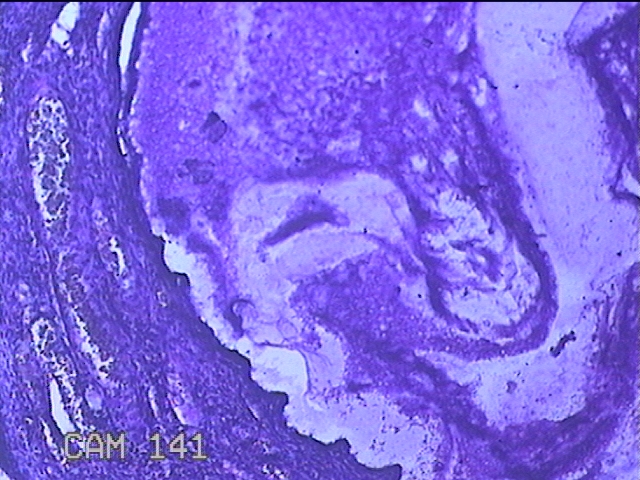

宫颈赘生物

性别

女

年龄

49岁

临床诊断

人乳头瘤病毒感染

一般病史

宫颈HPV阳性TCTLSLL

标本名称

大体所见

灰白粉红色肿物1.2x0.8x0.2cm两个,表面光滑。

图4